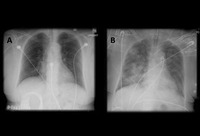

A. Portable upright chest x-ray before aspiration; B. Chest x-ray 1 hour after aspiration, showing bilateral diffuse alveolar infiltrates, worse at the bases on the right side

From the personal collection of Dr S. Murgu and Dr H. Colt, University of California at Irvine Medical Center